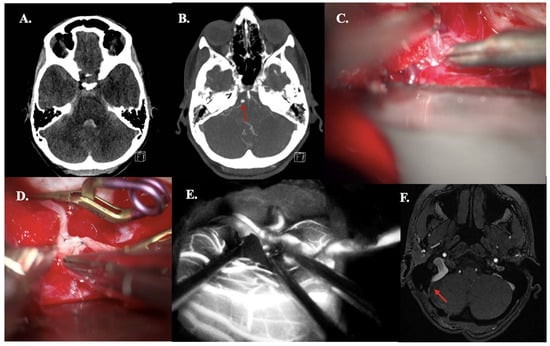

3.4.3. Case 19—Dissected Fusiform AICA Aneurysm

A 35-year-old woman presented with progressive headache and nausea with vomiting (WFNS grade II). CT demonstrated aneurysmal subarachnoid hemorrhage (mFisher grade II, based on thin aSAH and intraventricular hemorrhage) (Figure 5A). aSAH was caused by a dissected AICA aneurysm (fusiform, size: 4 mm), confirmed on CTA (Figure 5B). An OA-AICA bypass with endovascular parent vessel occlusion was performed. Intraoperative patency was confirmed using ICG videography (Figure 5C–E). At 3-month follow-up, bypass patency was confirmed by MRA, corresponding with the need for bypass maturation (Figure 5F). During hospitalization, she demonstrated abducens palsy, which completely resolved at the last follow-up.

Figure 5. Illustrative Case #19. 35-year-old female with aSAH caused by fusiform (4 mm) dissected AICA aneurysm with intraventricular hemorrhage. (A) CT scan demonstrating mFISHER grade II. (B) Maximum intensity projection of ultra-high-definition CTA, demonstrating AICA aneurysm (red arrow). (C) The AICA was dissected just above the internal acoustic meatus. (D) The occipital artery—AICA anastomosis back wall was performed. (E) ICG videoangiography confirms patency of the bypass. (F) Five-month follow-up Time of Flight MRA confirming bypass patency (red arrow).